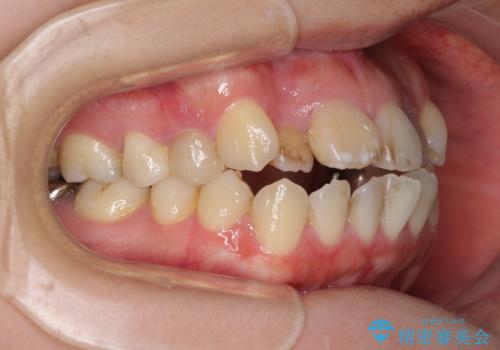

- 八重歯と前歯のデコボコ、開咬を気にして来院された患者様です。

抜歯矯正が必要であることはご自身で理解されており、目立たない装置をご希望であったので、上顎が裏側装置であるハーフリンガル装置にて治療を行うこととしました。

上顎前歯や下顎大臼歯に根管治療の必要な歯がいくつかあるため、矯正治療と並行して根管治療を行い、その後オールセラミッククラウンにて補綴治療を行うこととしました。